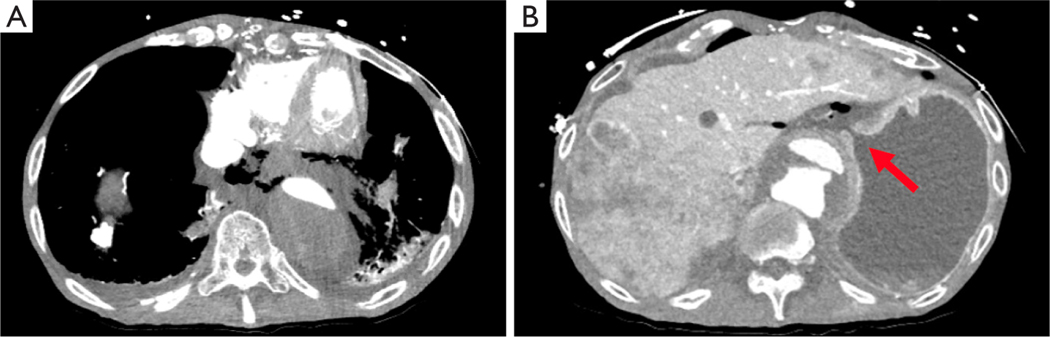

Case description: This case report details our experience with a moribund patient who was found to have extensive pneumomediastinum and gastric perforation secondary to black esophagus and black stomach. This was diagnosed on endoscopy following imaging that showed extensive pneumomediastinum. Initially the intent was to temporize the disease process in an attempt to stabilize the patient however at the time of diagnosis, the degree of ischemia had led to perforation and the disease process was not reversible or recoverable. He ultimately expired after comfort directed care measures were put in place.